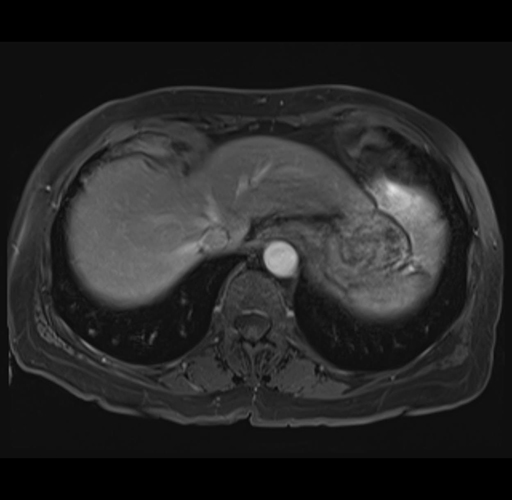

MRI T1